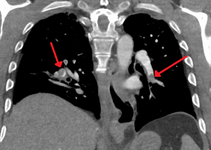

SaddlePE.PNG

Chest spiral CT scan with radiocontrast agent showing multiple filling defects both at the bifurcation ("saddle" pulmonary embolism) and in the pulmonary arteries